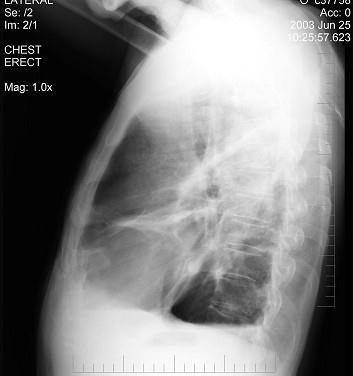

男性患者,62岁,常感胸闷、气逼,X线检查如图,最可能的诊断是 ( )A.右侧肺大疱B.右侧气胸C.右侧肺脓肿D.右侧胸膜肥厚E.气胸

问题 男性患者,62岁,常感胸闷、气逼,X线检查如图,最可能的诊断是 ( )

选项 A.右侧肺大疱 B.右侧气胸 C.右侧肺脓肿 D.右侧胸膜肥厚 E.气胸

答案 A